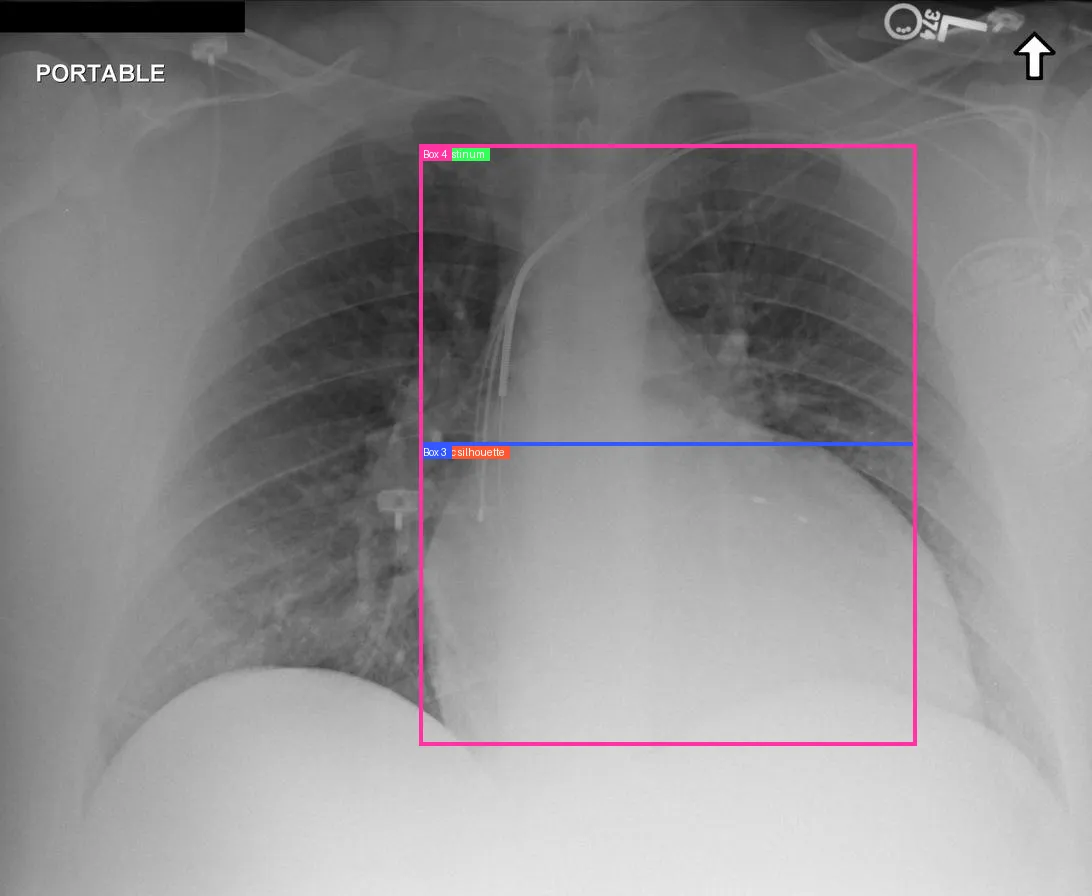

Think with Medical Image

To elevate the model’s visual reasoning ability in medical contexts, we introduce a specialized grounded reasoning paradigm centered on anatomical structures. Moving beyond generic object detection, this paradigm establishes anatomical landmarks as the fundamental anchors for vision-language alignment. It implements a structured Analyze-Reason-Conclude workflow that mirrors the clinical standard: The analysis phase strictly adheres to the radiological protocol, systematically traversing anatomical landmarks while interleaving textual findings with precise bounding box coordinates. This mechanism explicitly binds reasoning steps to visual evidence, bridging the modality gap. Based on these grounded observations, the reasoning phase synthesizes evidence to deduce pathologies, ensuring that every diagnostic conclusion can be traced to a specific visual region. By integrating this anatomy-centered paradigm, we transform grounding from a simple detection task into a structured, evidence-based reasoning process that significantly enhances the transparency and trustworthiness of the model’s clinical judgments (as shown in Fig. 11).

While anatomical reasoning provides the logical framework, visual limitations can hinder fine-grained detection. To address this, we integrated Think with Image [67, 22] design, enabling the model to perform secondary operations—such as rotating or zooming in—to facilitate a deeper understanding of visual information. This capability holds tremendous potential in medical imaging; for instance, zooming in on affected regions allows the model to perform granular inspection. Through exploration of tools in the multimodal domain, we identified Zoom in and Rotate as the most valuable primitives: the former is primarily designed for identifying subtle lesions in affected regions, while the latter assists with maintaining spatial orientation during the interpretation of complex medical images.

The training dataset is built mainly from radiology imaging data (e.g., X-rays, CT scans, MRI) and public de-identified radiology datasets, which include pathological/normal cases, metadata and expert annotations. Given the varying diagnostic complexity and tool utility of raw radiology data, a two-stage filtering pipeline is adopted to create an effective RL training set: